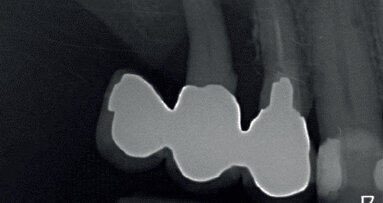

La cone beam rivela il mantenimento volumetrico del tessuto osseo periimplantare (Figg. 6a-6c). Questo case report evidenzia l’importanza della customizzazione delle cappette di guarigione per il mantenimento dei volumi dei tessuti perimplantari. La forma delle cappette di guarigione simili alle radici dei denti estratti avvitate sugli impianti post-estrattivi evitano il collasso volumetrico dei tessuti, guidando la guarigione dei tessuti perimplantari con il mantenenimento volumetrico dell’alveolo. Con questa metodica si riduce il numero delle procedure tradizionali eseguite per il trattamento implanto protesico negli impianti post-estrattivi. Si evita la riapertura del lembo gengivale, le varie fasi della ribasatura del provvisorio per il condizionamento gengivale, riducendo i tempi e i costi. Con questa procedura si lavora in modo conservativo, si velocizzano i tempi di esecuzione del flusso di lavoro mantenendo inalterati i parametri morfologici e volumetrici dei tessuti periimplantari. E tutto questo flusso di lavoro è possibile effettuarlo direttamente alla poltrona diminuendo i costi e il tempo per il paziente.

Fig. 6b, 6c - Le sezioni alla Cone beam mostrano il mantenimento volumetrico dell’osso alveolare.